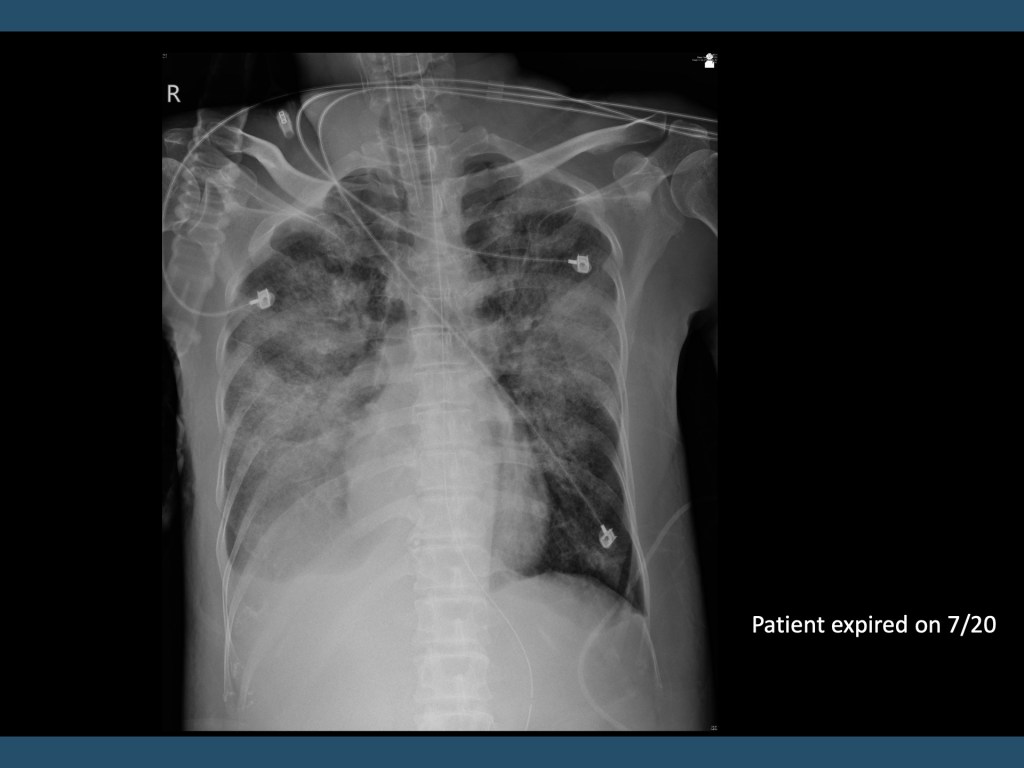

這次報告的case是一個中年男性,在這次住院新診斷紅斑性狼瘡然而在住院檢查的過程中開始出現罕見病發症。病人開始出現喘以及咳血的情形,X 光出現新的浸潤,後來咳血狀況惡化,插管後做支氣管鏡診斷了瀰漫性肺泡出血。然而在治療後病人的肺出血狀況沒有改善,並且很快出現敗血性休克而過世。

瀰漫性肺泡出血(diffuse alveolar hemorrhage)是紅斑性狼瘡少見嚴重併發症之一,有極高的致死率。目前對於他的病理機轉不是很了解,但可以從病理切面上進行簡單的分類。在紅斑性狼瘡病人相關的瀰漫性肺泡出血可以使用methylprednisolone以及cyclophosphamide治療,但在治療瀰漫性肺出血的同時需要注意可能的感染。